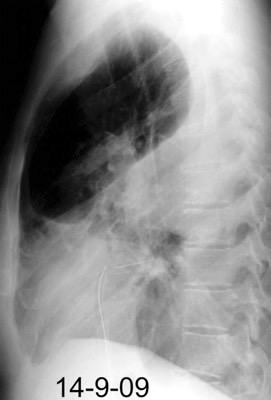

Neumonía a neumococos base izda. con derrame que aumenta.

Broncograma en lateral y en US.

(36-66% en ingresados)